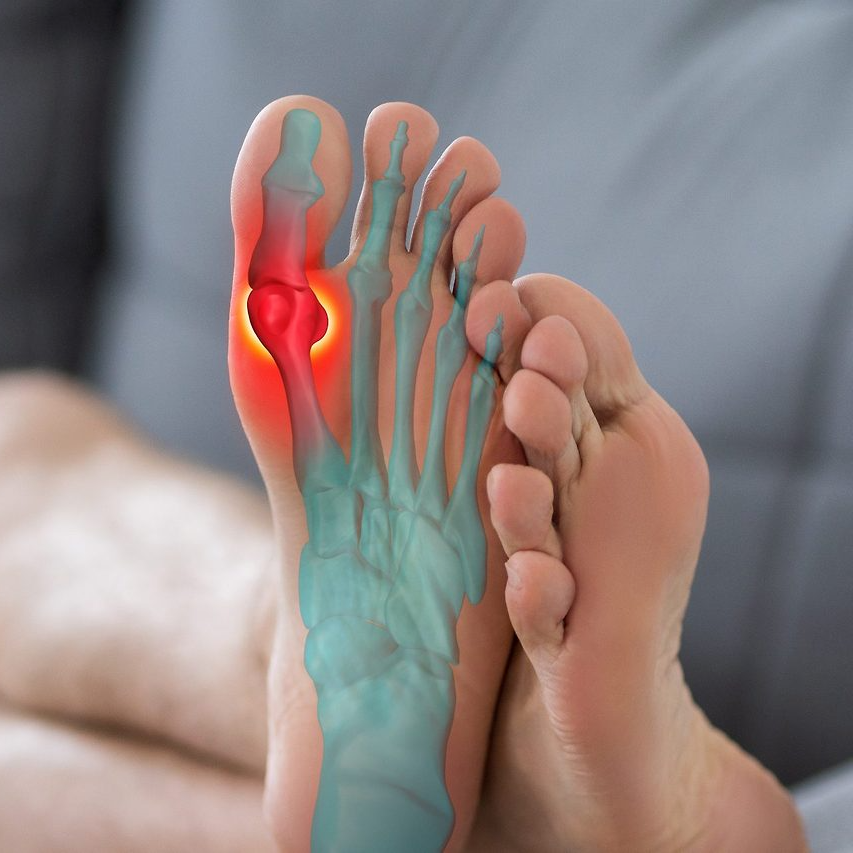

압축골절·폐쇄성골절·개방성골절 위로금 차이

보험에서는 골절의 유형에 따라 지급액을 달리 산정한다.

- 폐쇄성골절: 일반 골절로 분류되어 1회성 진단금 10만~20만 원 지급

- 압축골절: 중증으로 분류되며 위로금 20만~40만 원 가능

- 개방성골절: 수술이 동반되는 경우 많아 50만~100만 원 수준까지 확대

- 분쇄골절: 장기간 치료 필요 시 100만 원 이상 지급 사례도 존재

다만, 보험사가 요구하는 진단명은 ‘골절상세코드(S-codes)’에 따라 달라질 수 있다. 예를 들어, 새끼발가락 원위지골 폐쇄성골절(S92.54)과 개방성골절(S92.55)의 코드가 다르므로, 진단서에 코드가 명확히 기재되어야 보상이 원활하다.